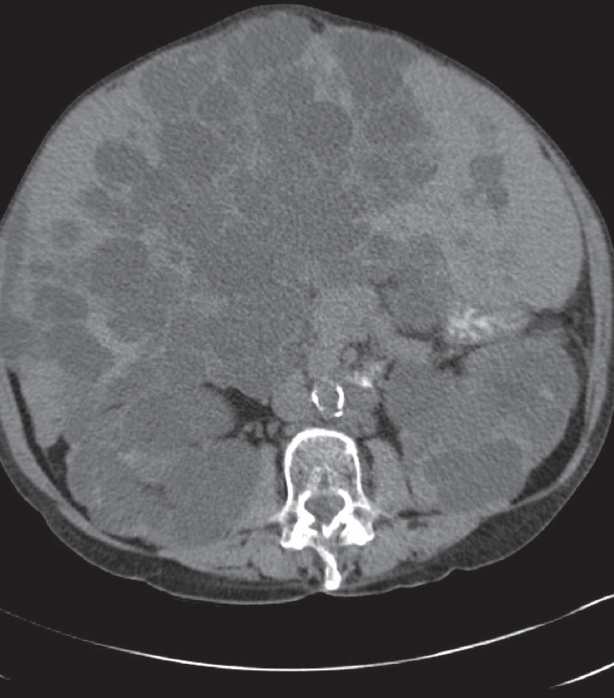

A 43-year old female with a history of autosomal dominant polycystic kidney disease (ADPKD) presented to the emergency room with a gradual onset of right upper quadrant abdominal pain for the past 7 days. ...